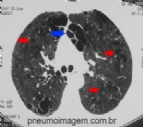

SEMANA DA SARCOIDOSE NA ATS

A semana da sarcoidose é uma iniciativa da American Thoracic Society, em colaboração com a Foundation for Sarcoidosis Research, que está sendo realizada estes dias para promover a investigação e a educação sobre a doença. A sarcoidose é...